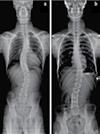

척추측만증(Scoliosis) / 척추협착증 / 허리수술 후유증

최첨단 목/허리 디스트 치료기기

Gonstead Chiropractic 교정치료

Southern California University of Health Science Doctor of Chiropractic 콜로라도주 척추신경 보드 정회원

척추신경과 보드 정회원 National Board 척추신경과 정회원 손석기 D.C. 원장, 척추신경 전문의 chiro1health@gmail.com Open Hours 월/수/금 9am-6pm 화/목: 2pm-6pm 청소년을 위한 척추교정 프로그램 척추 병원에서 풀타임 일하실 한국어 /영어 가능한 리셉션니스트 급구합니다